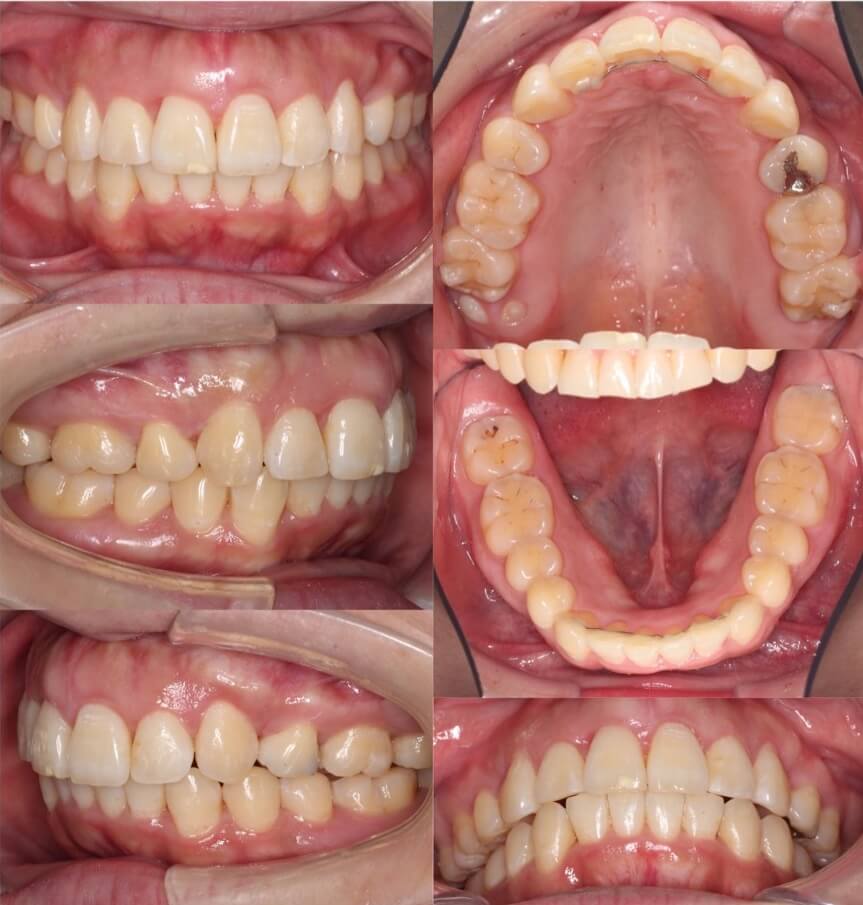

20代女性・ハーフリンガル装置・上下抜歯

上顎前突症に加えて、左側にシザースバイト(奥歯のすれ違い)症状もあるケースです。上の歯並びは裏側につける矯正装置のみでは対応できなかったため、奥歯のみ外側にブラケット矯正装置を装着しています。治療後は上の前歯が下唇にあたらなくなり、口が閉じやすくなりました。

<症例概要> 難易度:★★★★★

主訴:口元を引っ込めたい

年齢・性別:20代女性

住まい:千葉県八千代市

症状:下顎後退・上下顎前歯唇側傾斜・左側シザースバイト

治療方針:抜歯空隙の閉鎖(最大固定)

治療装置:ハーフリンガル矯正装置(上のみ裏側装置)

固定:歯科矯正用アンカースクリュー(口蓋側壁x2)

抜歯:上第一小臼歯・下第二小臼歯

治療期間:2年7か月

リテーナー:上下プレートタイプ+クリアタタイプ+フィックスタイプ

治療費用:1,320,000(税込)

代表的副作用:痛み・治療後の後戻り・歯根吸収・歯髄壊死・歯肉退縮

▶︎その他の副作用